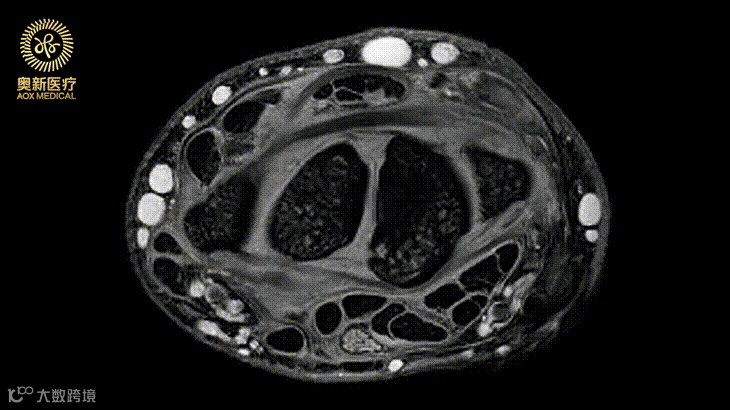

快速高分辨骨关节成像